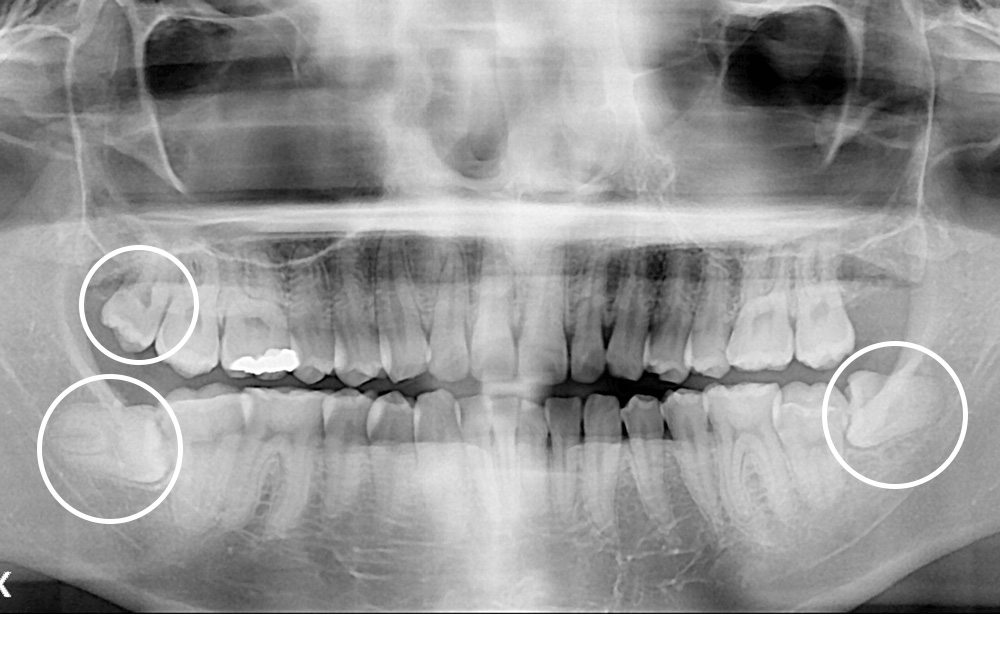

[사랑니] 매복 사랑니 발치

치료전 : 2020-02-24